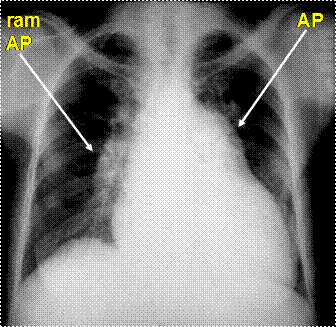

Rx cord-pulmon: circulatie pulmonara 'incarcata' cu ramurile AP dilatate in hiluri si extremitati 'retezate' avind periferie mult mai clara decat normal, bombare a conului arterei pulmonare, semne de hipertrofie VD

Imagine radiologica de HTP primara

Imagine radiologica de HTPS (DVPA) Imagine radiologica de HTPS (stenoza mitrala)

HTP secundara incipienta (DSA) HTPS severa (DSA Eisenmengerizat)